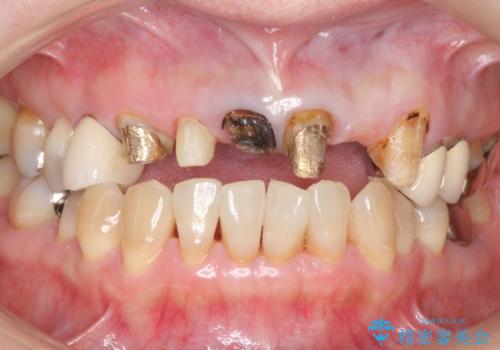

前歯のブリッジの下が虫歯 ブリッジのやりかえ

- 若い時に作った前歯のブリッジがの根元が黒くなってきているとのことで来院。

支える歯が1本虫歯がひどく、割れていました。

根の治療からやり直して新しいブリッジにしています。